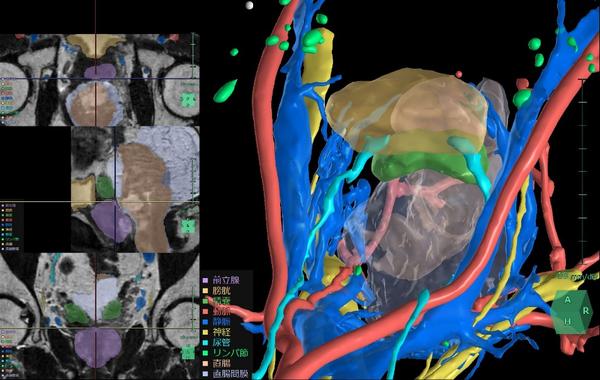

(2)膀胱周辺臓器解析

術前のCT画像やMR画像から3D構築を行うことで,骨盤腔内の膀胱周辺臓器や神経,血管の位置関係を把握し,患者ごとに異なる血管走行などの解剖学的特徴を把握し,手術シミュレーションを行うことができる。

すでに解析機能を提供している直腸と同様に, 骨盤内に位置する膀胱や前立腺の手術においても周囲の血管や尿管,臓器の位置関係の把握は非常に重要である。このニーズに対応して,骨盤内の泌尿器科領域に対応したアプリケーション「膀胱周辺臓器解析」を新たにリリースする。この機能により膀胱周囲の臓器や神経,血管の位置把握を支援することで,前立腺癌や膀胱癌手術時のリンパ節郭清等において手術リスクの低減と治療成績の向上への貢献が期待される。

膀胱周辺臓器解析の解析画面